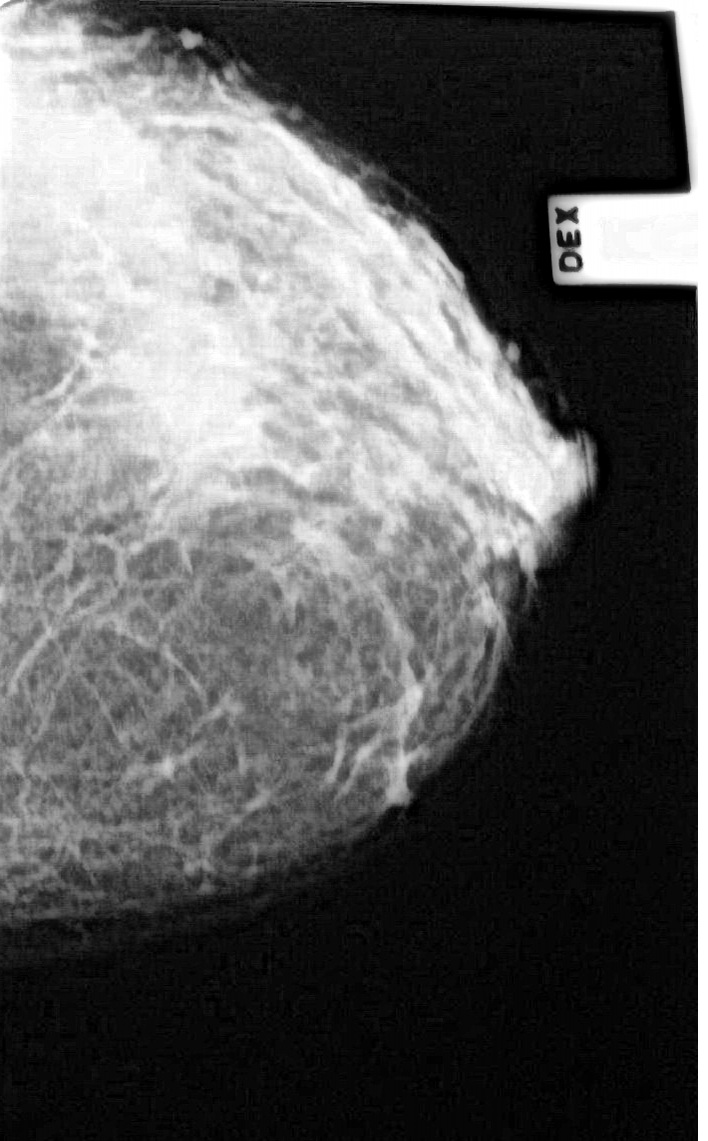

Что такое маммография: важность, процесс и результаты

Раздел: Необычные решения